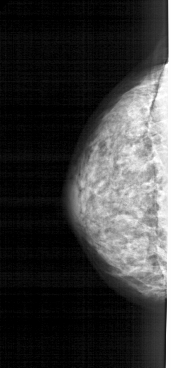

A_1269_1.LEFT_MLO

A_1269_1.LEFT_CC

LEFT_MLO LINES 4966 PIXELS_PER_LINE 2086 BITS_PER_PIXEL 12 RESOLUTION 43.5 NON_OVERLAY

LEFT_CC LINES 4411 PIXELS_PER_LINE 2041 BITS_PER_PIXEL 12 RESOLUTION 43.5 NON_OVERLAY